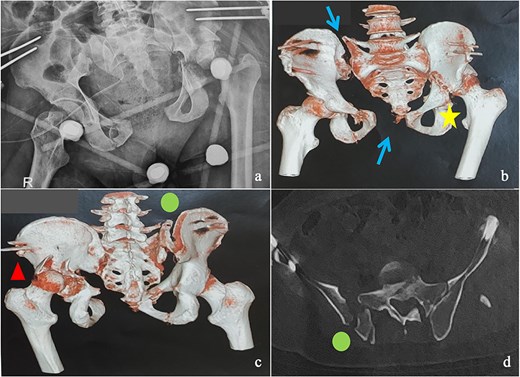

(a) Anteroposterior pelvic X-ray showing delayed pelvic and acetabular fractures. (b) Anterior view of the pelvis on 3D section: pubic symphysis disjunction and right sacroiliac dislocation (arrows), transverse component of the left acetabular fracture (star). (c) Posterior view of the pelvis on 3D section: right crescent fracture associated with right sacroiliac dislocation (circles), fracture of the posterior wall of the left acetabulum associated with posterior dislocation of the femoral head (triangle). (d) Axial section of the pelvic CT-scan: right crescent fracture Kumar-Day 2 (green arrow).

This was a 42-year-old male patient with no previous medical history who was admitted to the intensive care unit for treatment of polytrauma: severe chest trauma and pelvic trauma. During his stay in intensive care, the patient developed a pulmonary infection complicated by septicemia, requiring prolonged antibiotic therapy and thereby contraindicating any internal surgical fixation. After hemodynamic and respiratory stabilization, he was transferred to our department 40 days after the trauma with the following injuries: an unstable pelvic ring fracture classified as Tile-AO B1-2 [4]: disjunction of the pubic symphysis, disjunction of the right sacroiliac joint, and an ipsilateral crescent fracture classified as Kumar-Day 2 [5], along with a transverse–posterior wall fracture of the left acetabulum associated with a posterior dislocation of the hip, which was initially reduced but remained unstable. Fixation was performed using a Hoffmann II external fixator applied to the iliac crests with poor reduction (Fig. 1). He presented with complete weakness of the left foot dorsiflexors, with preserved sensation and no urogenital or abdominal complications. ORIF was performed in two stages, 5 days apart. The first stage consisted of performing the first two windows of the ilioinguinal approach: the lateral window to access the sacroiliac joint and the middle window to access the lower part of the sacroiliac joint and remove the osteofibrous callus. A Pfannenstiel approach was used to remove the callus at the pubic symphysis and fix it with a plate. The patient was then placed in the prone position and a posterior approach to the right sacroiliac joint was performed to carry out the same procedures on the posterior part of this joint and to perform fixation using ilioiliac and iliosacral screws. The second stage of the operation involved acetabular surgery. Given the chronic dislocation of the left hip, an anterior approach to the hip was performed to remove the intra-articular fibrosis facilitating the subsequent reduction of the femoral head. A Kocher-Langenbeck approach was then performed to remove the callus, reduce the femoral head and fracture, and fix it with a plate (Fig. 2). Postoperatively, the patient retained neurological deficits. At 6 months, the patient was able to walk without assistance and had a Harris Hip Score (HHS) score of 80 and Majeed score of 75 [6, 7].